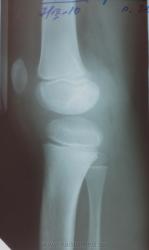

Мальчик 9 лет. Направлен на КТ коленных суставов с целью исключить туберкулёзный процесс. В конце июля сего года поступил в детскую больницу с диагнозом гнойный артрит правого коленного сустава. Делали пукцию, получили гной. Анализа содержимого не знаю. Начало острое, лихорадка до 39. После 2-ух недельного лечения улучшение, выписан в удовлетворительном состоянии. На сегодняшней день боли в колене не беспокоят, лихорадки нет. Консультирован фтизиатром, рекомендована КТ. Туб. пробы незнаю делали?, нет? Видел анализ крови от начала сентебря - норма. Детей снимаем очень мало. Ваше мнение?

23.07.2010г.

Да, структура латерального мыщелка бедра изменена, краевой дефект заднего контура с костным фрагментом, вокруг уплотнение структуры. Изначально такого не было. Даже не знаю, что это, на туберкулез не похоже. Может краевая деструкция вследствие гнойного артрита или что-то типа асептического некроза. Мне такое не попадалось. Надо подумать.